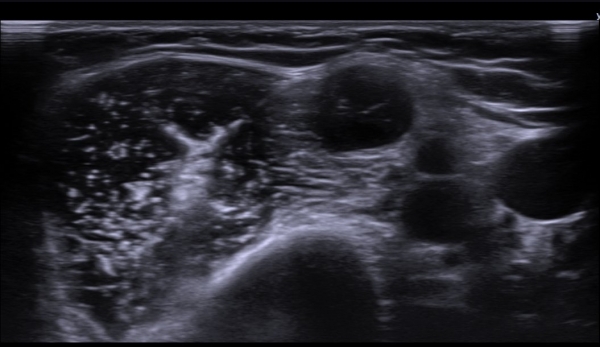

ÃÊÀ½ÆÄ  °Ë»ç  : À­ÆÈ ±ÙÀ§ºÎ Á¤Áß ½Å°æ Ⱦ´Ü¸é°Ë»ç¿¡¼­ Á¤Áß ½Å°æÀÇ ºÎÁ¾°ú ÀϺΠ½Å°æ¼¶À¯ÀÇ Àú¿¡ÄÚ ºÎÁ¾ÀÌ °üÂûµÈ´Ù

(»çÁø 1, 2). ŽÃËÀÚ¸¦ Á¶±Ù ´õ ±ÙÀ§ºÎ·Î À̵¿ÇÏ´Ï Á¤Á߽ŰæÀÇ Àú¿¡ÄÚ ºÎÁ¾ÀÌ °üÂûµÈ´Ù(»çÁø 3, 4).